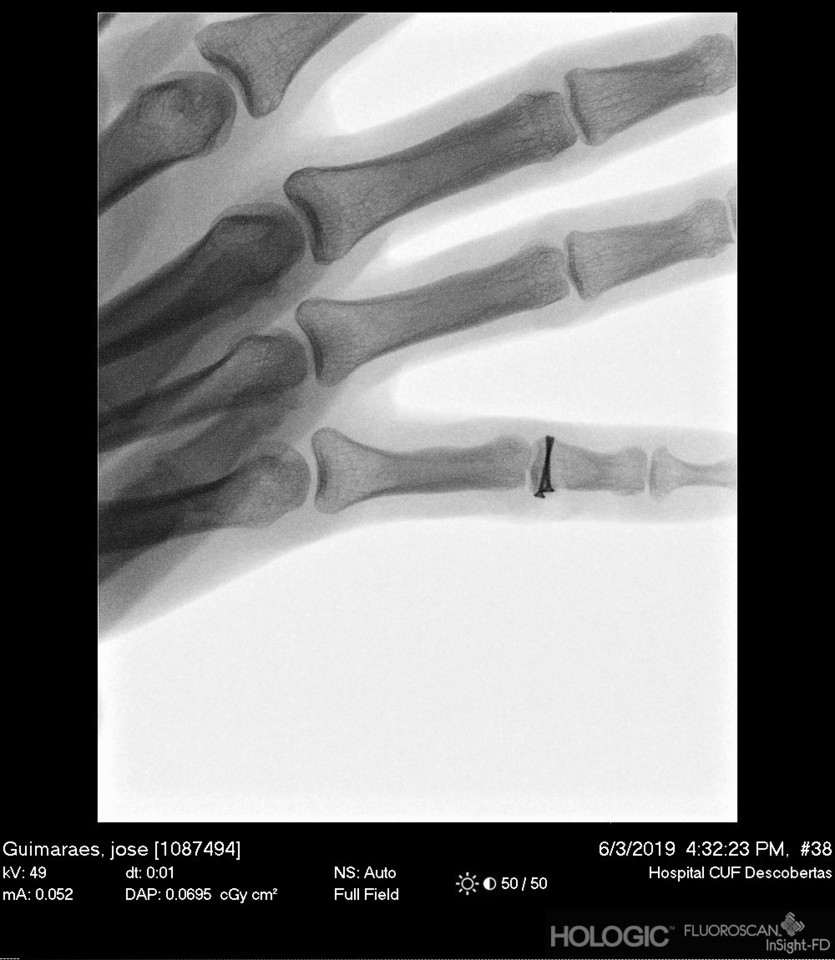

Daqui para a frente poupo-vos os detalhes. Sim fiz a TAC. Sim o meu dedo afinal tinha duas falanges rachadas a meio, com envolvimento da articulação (quer isto dizer que a até a cartilagem estava meio partida) e não só fui à faca, como tive que levar dois parafusos no dedo para solidificar melhor a coisa! Parafusos num dedo... eu?! Oh deuses...